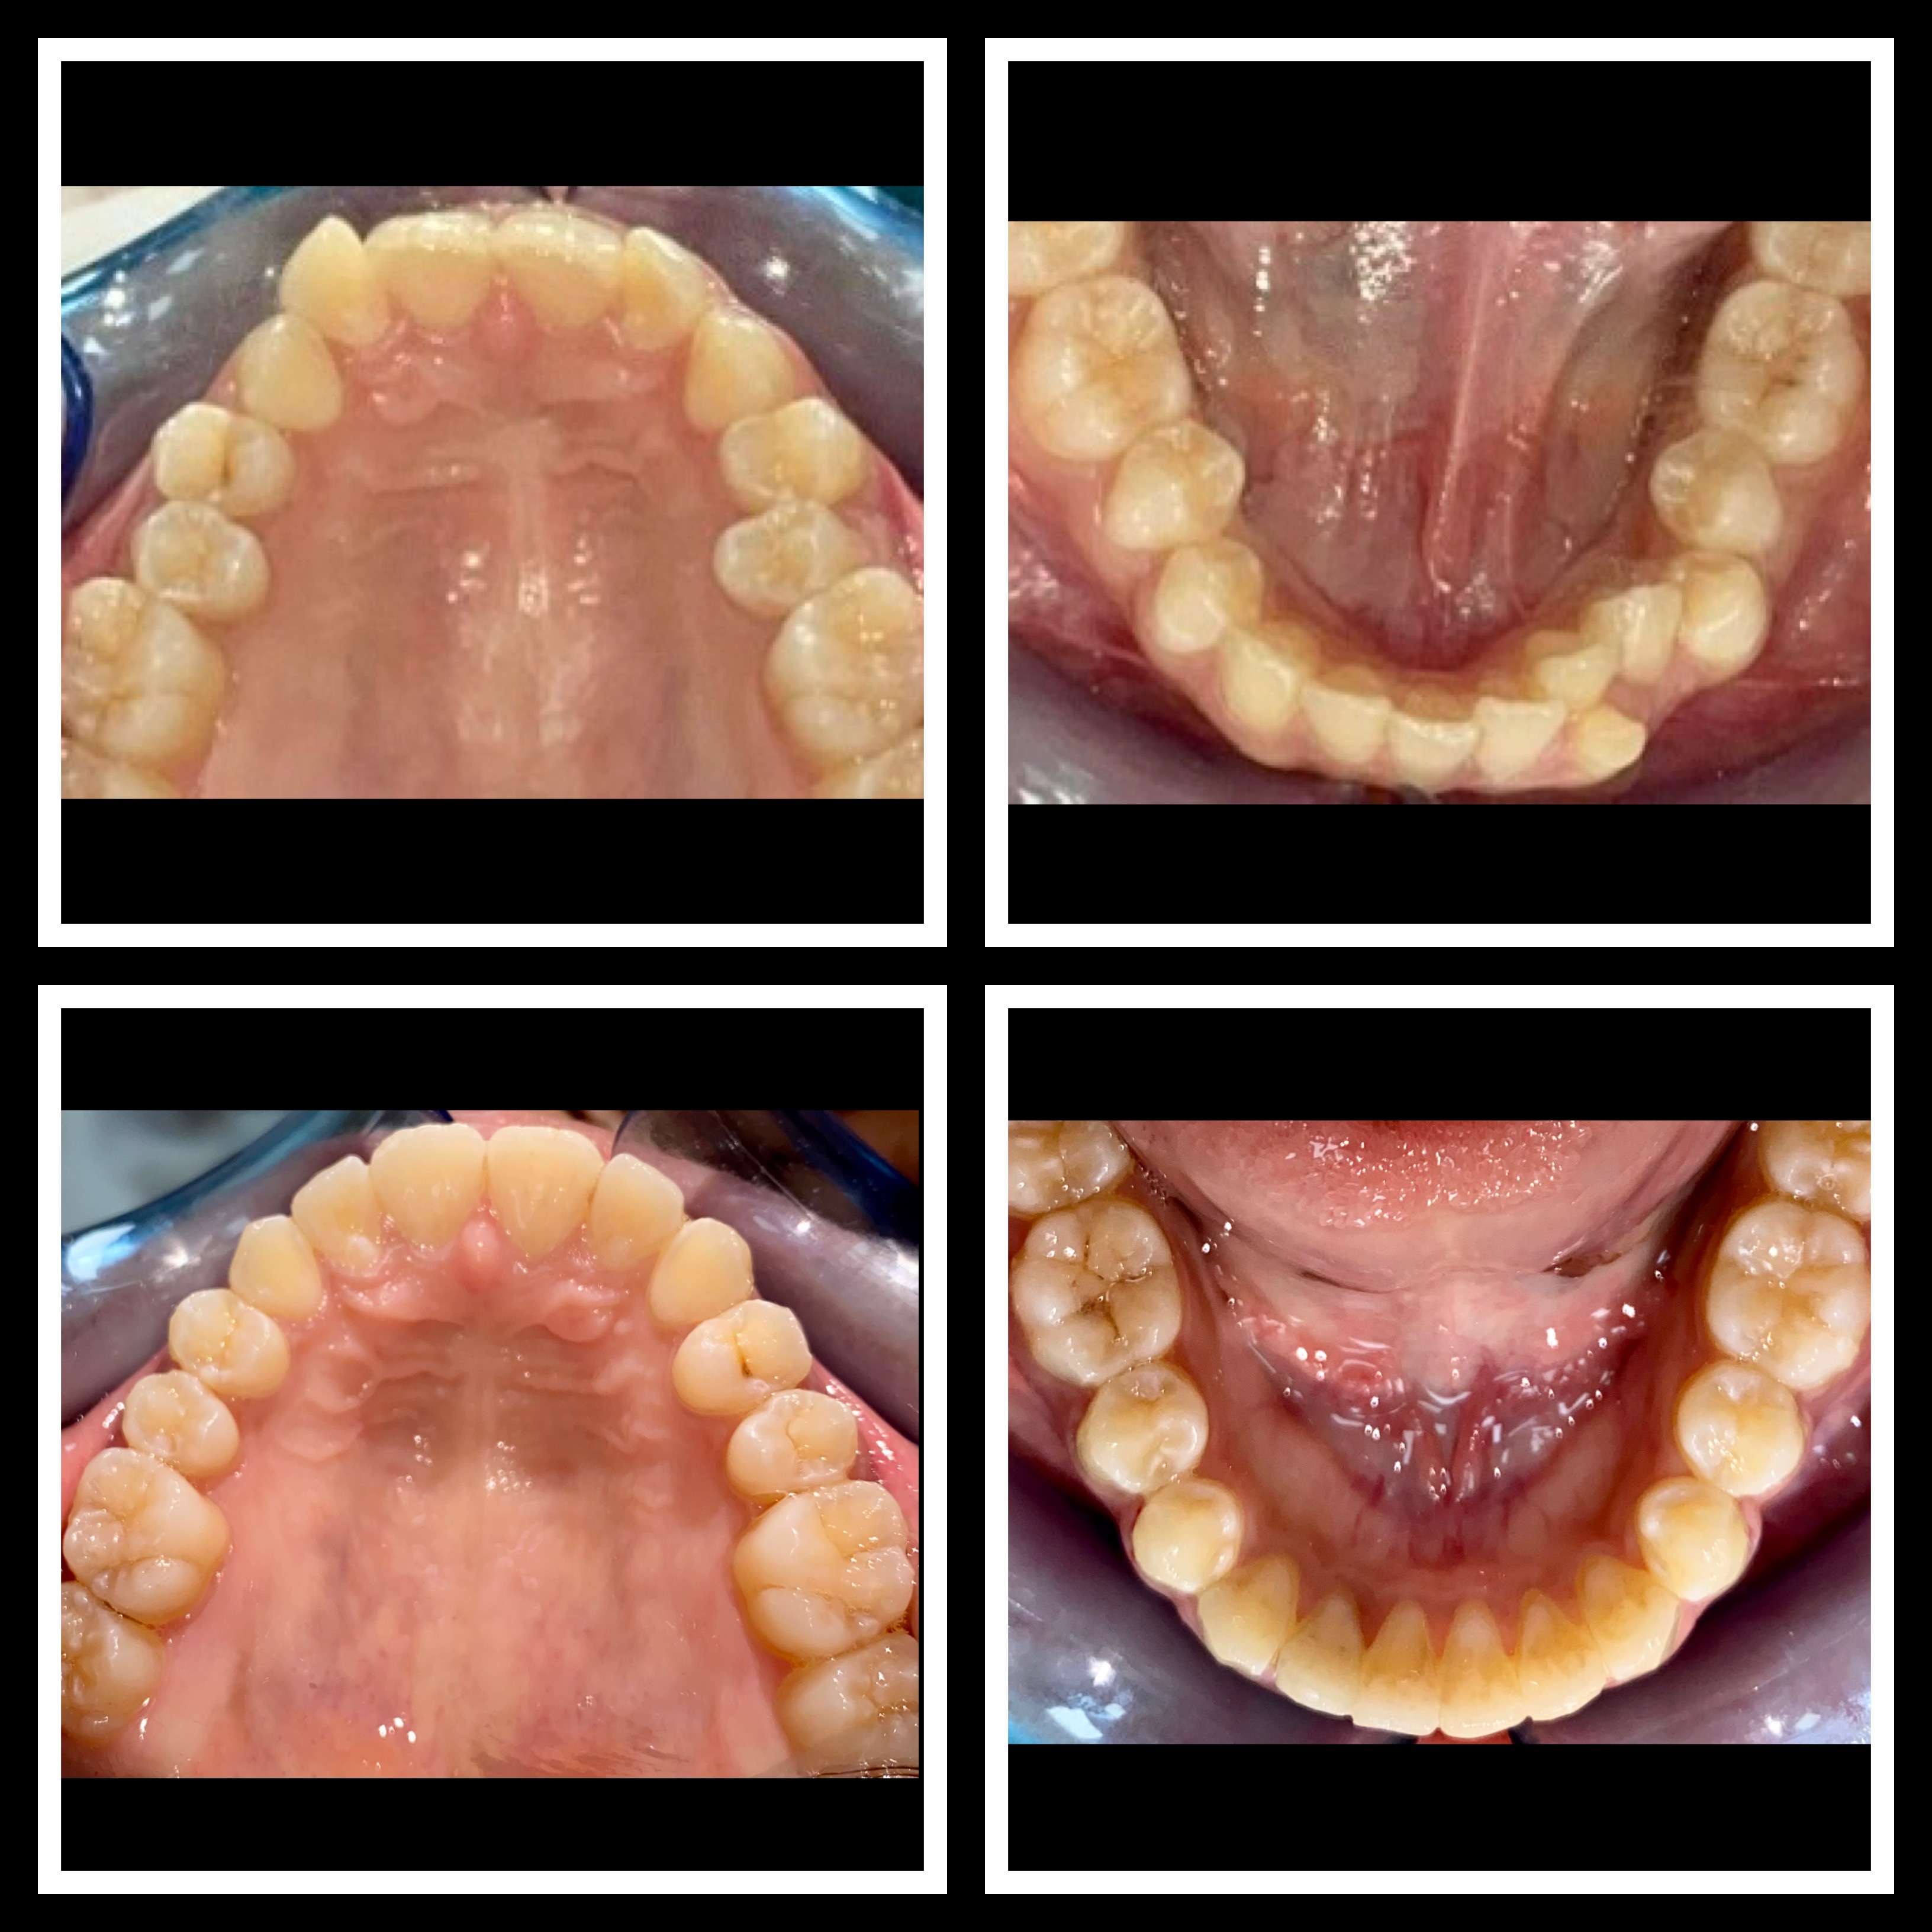

Gallery